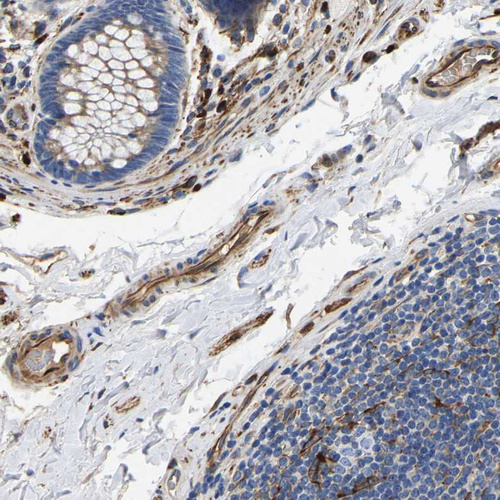

Immunohistochemical staining of human cerebral cortex shows strong cytoplasmic positivity in endothelial cells and glial cells.